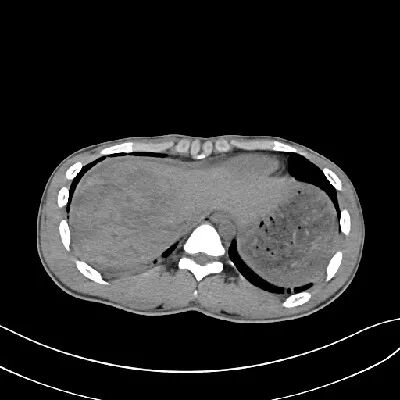

肝挫裂伤

[病因病理]

肝挫裂伤主要是指腹部受到外在力量的撞击而产生的闭合性损伤,是常见的腹部严重创伤,多由高处坠落、交通意外等引起。

[临床表现]

患者可有患部疼痛,但严重者多以失血性休克、腹部膨隆为首发症状。

CT表现:

对于肝损伤CT能确定其存在及范围,且有非常高的特异性。肝包膜下血肿会形成新月形或半月形的低密度或等密度区,相应的肝实质会受压变平而显示肝表面的边界失去正常的弧形而变平,尤其血肿新鲜时其CT值与肝实质类似,此时注意肝表面周缘的改变亦就显得重要。

一般来讲,血肿的CT值随时间的推移而减低。在肝实质的血肿则常常显示圆形、卵圆形或星状低密度影。肝撕裂会见到单一或多发的线样低密度,边缘模糊。

[鉴别诊断]

肝包膜下血肿形成的新月形或半月形的低密度或等密度区,需与腹水围绕肝周围鉴别。通过外伤病史及密度测量不难鉴别。